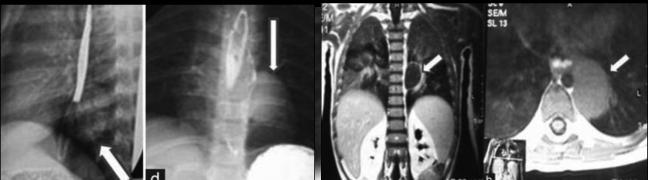

- Duplication

congenitale de oesophage: C'est malformation

congenitale en formation kystique spherique ou tubulaire

au contact de oesophage . Sa situe est 60% a 1/3

inferieurede oesophage , 17% au 1/3 moyen et 60% pour le

1/3 inferieure

Image IRM en T1 et T2 une duplication kystique

1/3 inferieure de oesophage ( coupe frontale et

coupe horizontale ) . Cliche de face et de profile a

droite se presente uimage image de duplication

kystique de oesophage situe a 1/3 inferieure de

oesophage |

Image TOGD de

oesophage une duplication tubulaire de oesophage

|

Image CT scanner une

duplication tubulaire de oesophage ( coupe tranverse

, fenetre parechymateuse ) |